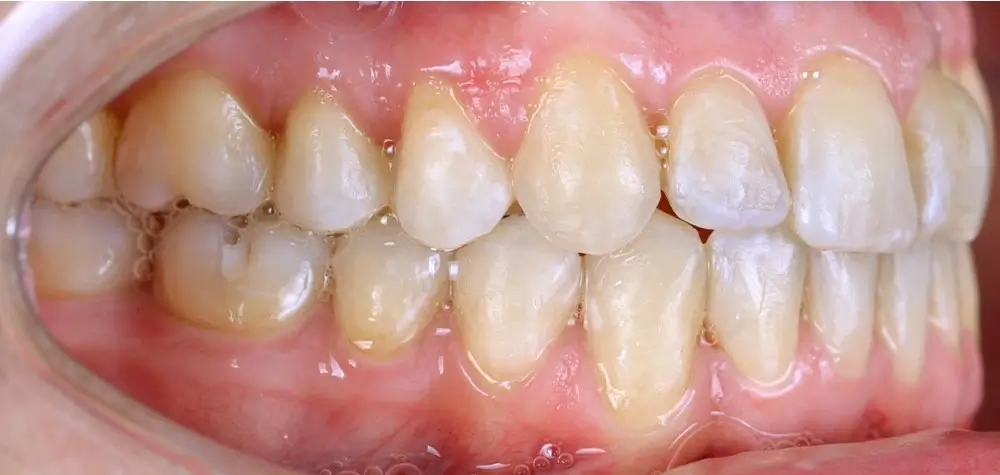

Кейс 4

Бажанова Ольга Валерьевна

Количество кап ВЧ 35

Количество кап НЧ 35

ДО

ПОСЛЕ